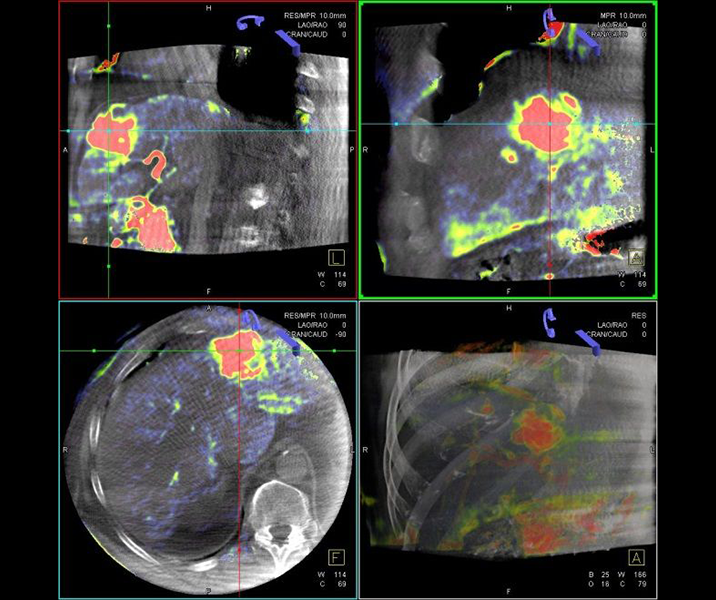

Bei der perkutanen Thermoablation von Nierentumoren werden spezielle Applikatoren unter CT- oder MRT Bildgebung in den Zieltumor eingebracht. Durch Hitze wird der Tumor zerstört.